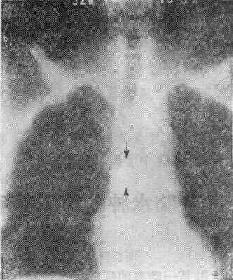

113-3 气道肿瘤(两箭头之间)

(四)占位性病变 ①血肿、脓肿是较常见的原因,如咽后壁脓肿;②肿瘤(图113-37),管腔内或管壁良恶性肿瘤如错构瘤、血管瘤和癌等;③气道附近组织器官的肿瘤,如甲状腺的肿瘤压迫侵犯气道。这类原因引致的气道梗阻,一般是慢性进行性的。然而当气道狭窄的程度超过管径的75%以上,由于附加因素如粘痰等可导致急性气道梗阻,产生严重的呼吸困难,甚至窒息死亡。④异物吸入气官。